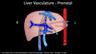

Normal Fetal Cardiac Anatomy: The Great Vessels & Upper Mediastinum

Alfred Abuhamad, M.D.